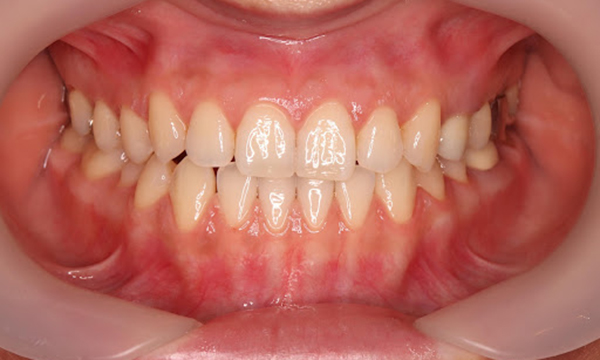

症例4

before

症例

after

年齢・性別 26歳・男性

主訴 主訴:左下親知らず痛い

治療部位:左下8番

治療内容 ・左下8番埋伏抜歯

治療方針 左下の親知らずが痛いとのことでご来院された患者さまです。

親知らず周囲は汚れが落としきれておらず、歯ぐきが炎症を起こしている状態でした。

当日抜歯を希望されていたので、麻酔を効かせてから三次元的なレントゲン写真(CT)撮影し、抜歯を行いました。

その後、全顎的に歯石付着、歯ぐきの炎症が見られたので歯周病治療をその他の治療と並行して行っていきました。

担当者所見 初診時は歯ブラシの交換時期を把握していなかった患者さまが歯ブラシを新しくしてから約1ヶ月後自分から歯ブラシを変えたことを教えてくださいました。

歯周病治療を進めていくうちに、患者さまの口腔内への意識が高まっていて治療が良い方向に進んでいきました。

歯周基本治療とセルフケアで歯ぐきの炎症や出血は初診時より大分改善されましたが、出血率を0%まで減らしていけるように今後は定期的な検診で歯ブラシの当て方や経過を患者さまと一緒に確認していこうと思います。